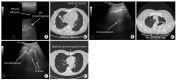

Results: We included 17 studies, reporting a total of 274 patients with M. pneumoniae, 30 with fungal infection and 213 with pulmonary tuberculosis (TB). Most of the studies on M. pneumoniae in children found a specific LUS pattern, mainly consolidated areas associated with diffuse B lines. The typical LUS pattern in TB consisted of consolidation and small subpleural nodes. Only one study on fungal disease reported LUS specific patterns (e.g., indicating "halo sign" or "reverse halo sign").

Conclusions: Considering the preliminary data, LUS appears to be a promising point-of-care tool, showing patterns of atypical pneumonia and TB which seem different from patterns characterizing common bacterial infection. The role of LUS in the diagnosis of fungal disease is still at an early stage of exploration. Large trials to investigate sonography in these lung infections are granted.